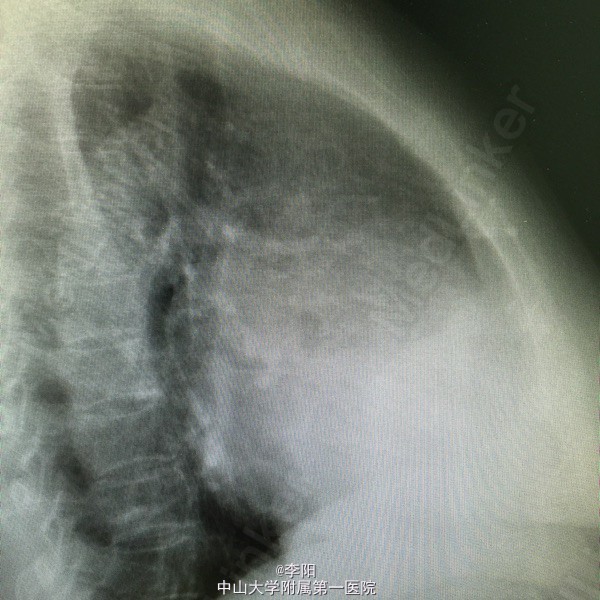

风湿性心脏病一例

风湿性心脏病

该患者一年前出现劳力后气促,走路1000米后可出现,当时无胸闷,胸痛,心悸等症状,伴有双下肢轻度水肿,未予诊治。6月前患者上述症状明显加重,走路200米即可出现气促,伴胸闷,心悸等症状双下肢开始出现重度水肿。